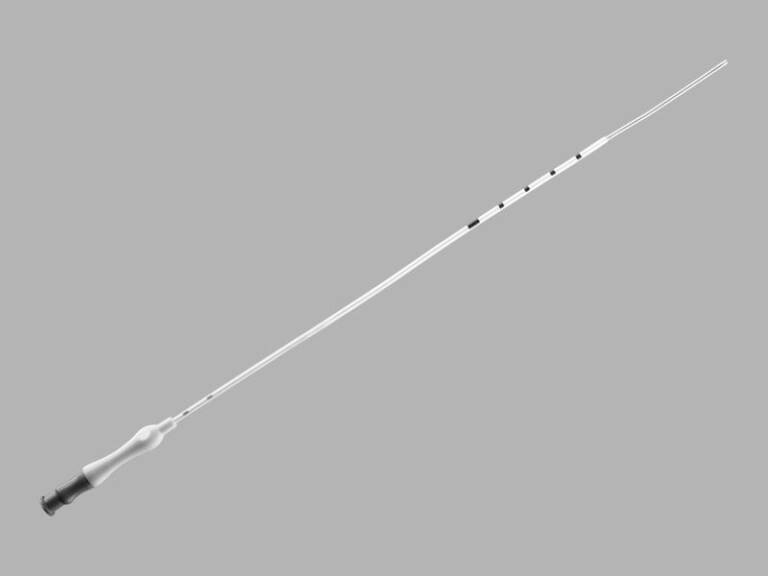

Cook® Soft-Pass Embryo Transfer Catheter Set

DESCRIPTION:

Used to place in vitro fertilized (IVF) embryos into the uterine cavity.

- The soft, flexible guide catheter is designed to facilitate placement of the set.

- Sets are available with transfer catheters that have an integrated stainless steel support cannula to aid catheter placement.